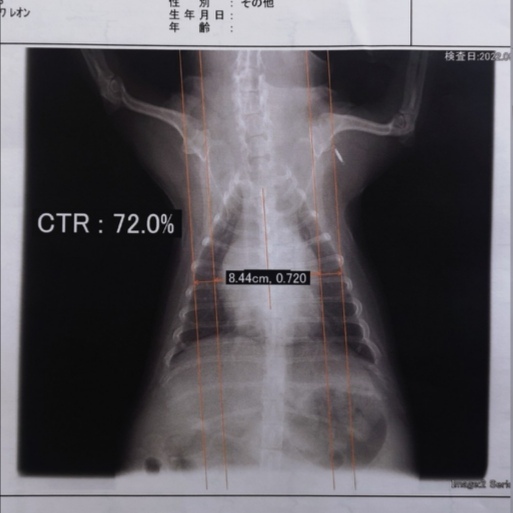

【僧帽弁閉鎖不全症】

この病気にはA~Dまでの五段階のステージがありますが、レオンは二番目に重篤なCです。

「心臓僧帽弁閉鎖不全症」